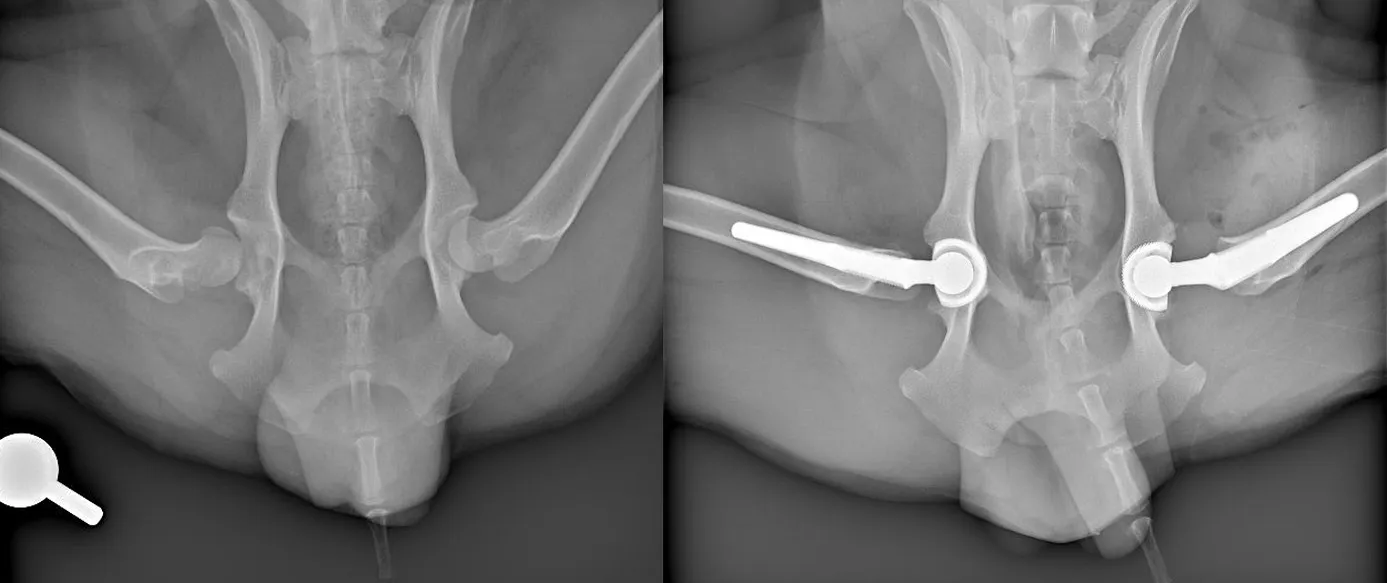

xrays of dogs hips before and after double hip replacement surgery

Xrays showing Theo's hips before and after two hip replacement procedures to replace his misshaped femoral head and hip sockets with prosthetics

X-rays confirmed that Theo was a suitable candidate for a total hip replacement and he was scheduled to have the procedure on his right hip joint, which was the worst affected of the two.

Once under general anaesthetic, the orthopaedic surgeons removed the femoral head - the ball of the hip joint - from the top of Theo’s femur and replaced it with a metal prothesis. The acetabulum of his pelvis, also known as the hip socket, was replaced using a prosthetic cup implant for the artificial femoral head to sit into.